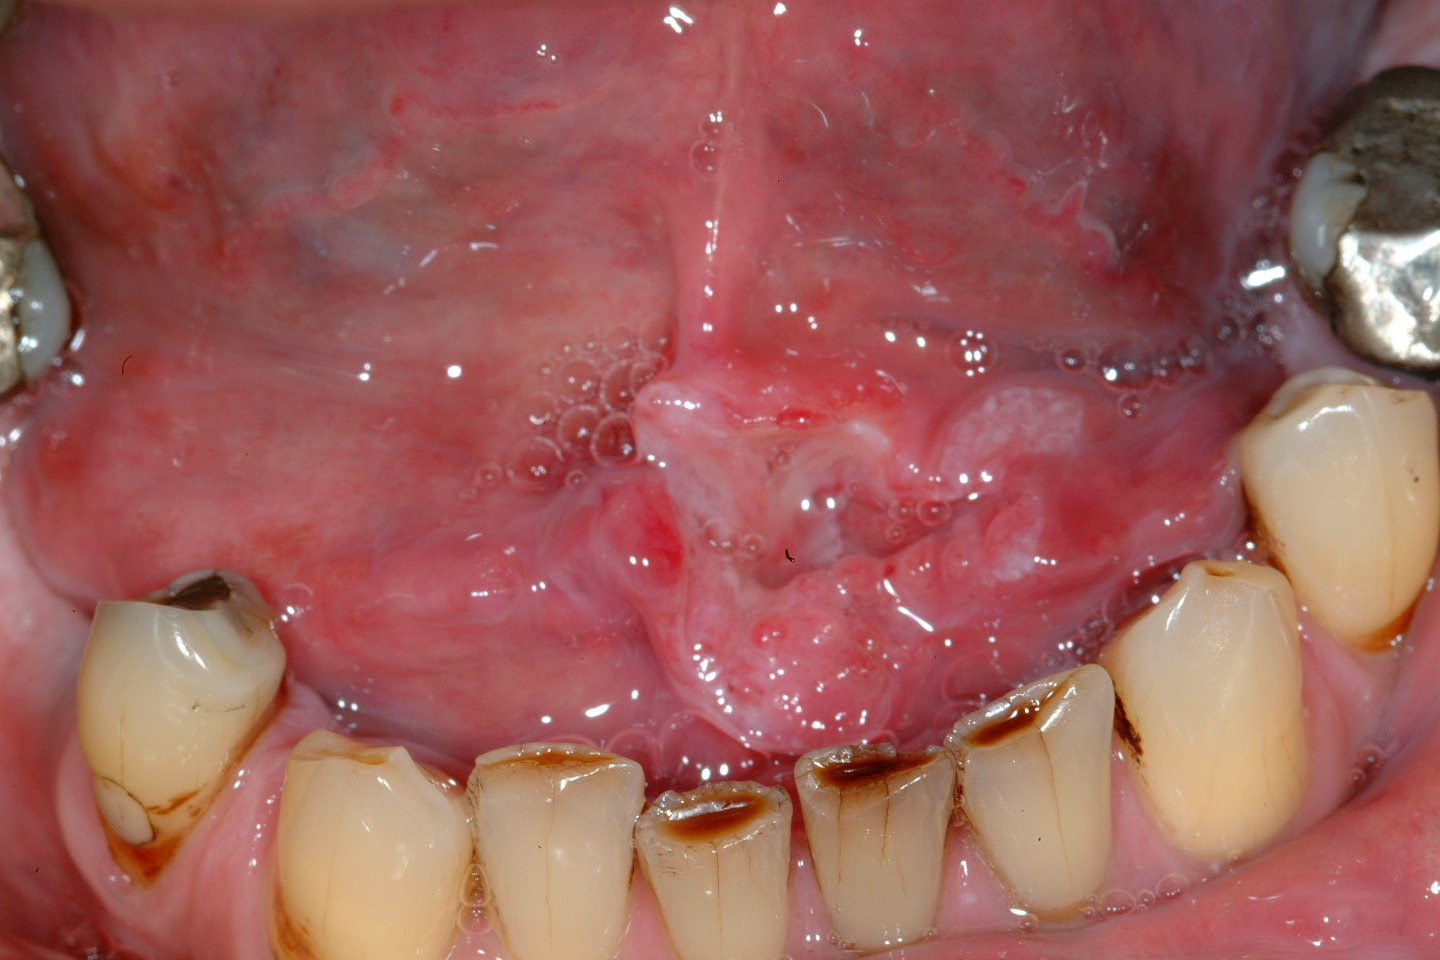

Figure 1: An example of squamous cell carcinoma of the left anterior floor of mouth.